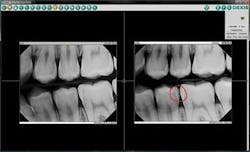

Digital imaging is a valuable educational tool, because images appear almost instantly on the screen. With a click of my computer mouse, I can compare side–by–side the patient's older and newer images.

I always say, “Seeing is believing,” and digital technology raises my diagnostic capabilities and treatment planning to a higher level.

When I can sit beside a patient and with the click of a mouse point out on the monitor the exact spots where the decay has gotten deeper, the patient is more likely to accept treatment.

Even better, the sharp contrast delivered when I enhance images with my DEXIS ClearVu™ allows the patients to see their issues as clearly as I can. Patients appreciate their shorter appointments as well as the reduced radiation of digital imaging over traditional methods. I can easily and quickly e–mail digital X–rays to my colleagues for consultation. Financially strapped patients appreciate the fact that your technology avoids scheduling an unnecessary trip to a specialist.